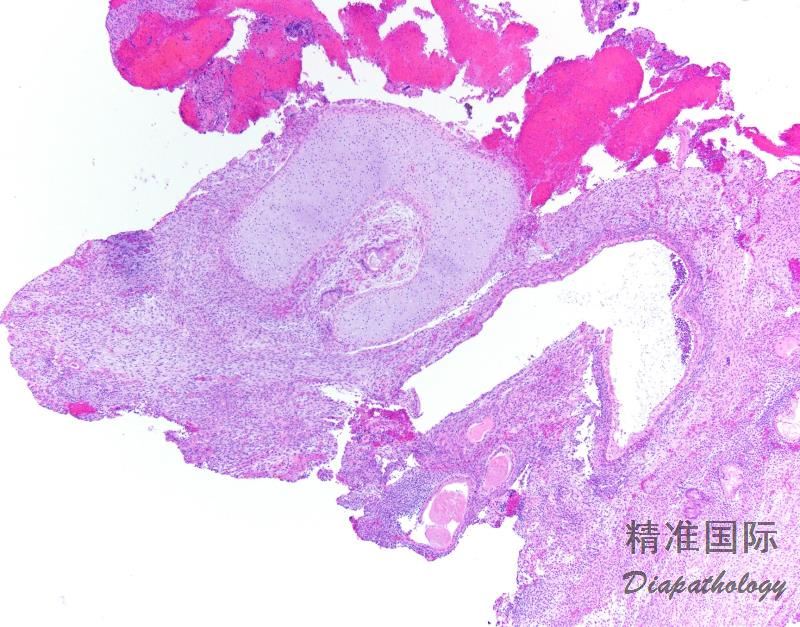

2. 肿瘤内遍布管状腺体和裂隙样腔隙,衬覆上皮的乳头状间质由表面突入囊腔,导致叶状肿瘤样外观;

7. 腺体周围间质细胞丰富是腺肉瘤的特征性表现,几乎每个病例都可见细胞丰富的袖套样间质围绕腺体或在表面上皮下方形成富于细胞的间质条带,至少局部如此;